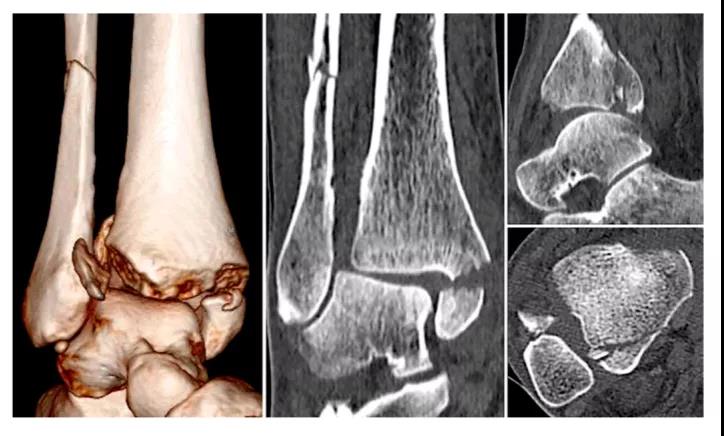

⑧ 复位后典型病例图。